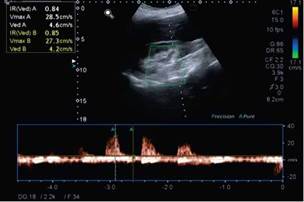

Immunoglobulins A, G, and M were normal; hematuria (150 erythrocytes/field) and proteinuria (750mg proteins in 24 hours) were found in urine, although proteinuria in the 24-hour urine for Bence Jones was negative. The albumin-to-creatinine ratio was 160 mg/g, and the protein-to-creatinine ratio was 760 mg/dL, and renal echo-Doppler showed an increase in resistance rates of intraparenchymal arteries (Figures 2 and 3).

Source: Document obtained during the course of the study.

Figure 2 Renal Doppler ultrasound of the right kidney.